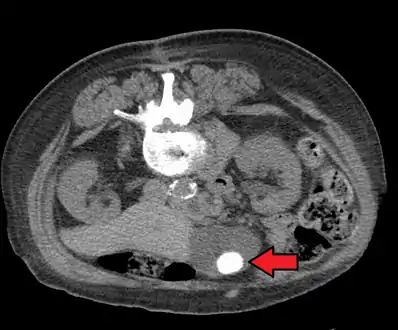

Diagnosis is typically confirmed by abdominal ultrasound. Other imaging techniques used are ERCP and MRCP. Gallstone complications may be detected on blood tests.[2]

On abdominal ultrasound, sinking gallstones usually have posterior acoustic shadowing. In floating gallstones, reverberation echoes (or comet-tail artifact) is seen instead in a clinical condition called adenomyomatosis. Another sign is wall-echo-shadow (WES) triad (or double-arc shadow) which is also characteristic of gallstones.[38]